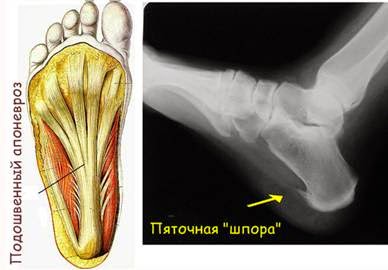

Пяточная шпора – это костный нарост в виде шипа или клина в области подошвенной поверхности бугра пяточной кости. Возникает он в месте прикрепления к пяточной кости подошвенной фасции и сухожилий мышц стопы. Подошвенная/плантарная фасция (или подошвенный апоневроз) представляет собой очень прочную, плотную соединительнотканную мембрану, которая начинается от бугра пяточной кости и прикрепляется к головкам плюсневых костей. Функция ее состоит в поддержке продольного свода стопы, аналогично тому, как тетива поддерживает стрелковый лук в согнутом состоянии.

Подошвенная фасция прикреплена к пяточному бугру и головкам плюсневых костей. Это служит поддержкой продольного свода стопы.

Диагностировать пяточную шпору может врач-хирург, хирург-ортопед. Для этого врач осматривает стопу визуально, а также может назначить рентгенографию. При этом рентген-снимок стопы позволяет подтвердить или опровергнуть наличие пяточной шпоры в области пятки. После чего назначается лечение.

Рентген-снимок стопы